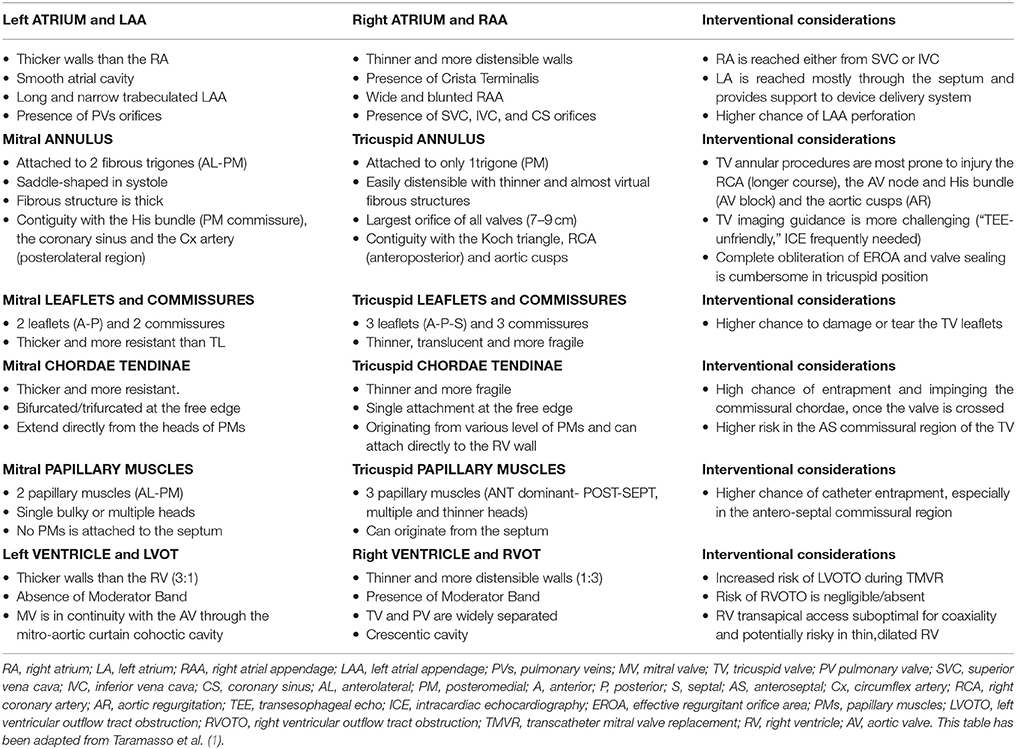

The tricuspid valve consists of three flaps or leaflets however cases are found when the tricuspid valve consists of only two or even four leaflets instead of the traditional three. The tricuspid valve lies within the right trigone.

The space in between the septal insertion of the tricuspid valve and the septal insertion of the anterior leaflet of mitral valve belongs to the membranous septum that separates the left ventricle from the right atrium.

Anatomy of the tricuspid valve. The tricuspid valve complex consists of the annulus leaflets right ventricle papillary muscles and chordae tendinae. Right atrioventricular valve tricuspid valve these are large veins that transport deoxygenated blood from the body back to the heart.

A greater appreciation of normal and abnormal anatomy is important as new methods of treating the tricuspid regurgitation are developed. It opens during diastole and closes during systole. The tricuspid valve tv is a complex structure.

B the relevant anatomy shown from the front view. The tricuspid valve lies between the right atrium and the right ventricle and is placed in a more apical position than the mitral valve. The tricuspid valve has an area of 4 to 6 cm square and is located between the right atrium and the right ventricle of the heart.

The valve has anterior posterior and septal leaflets cusps the bases of which attached around the av orifice to the fibrous ring fibrous skeleton of the heart. Blood collects within the right atrium and it must flow through the tricuspid valve in order to enter the right ventricle. The tricuspid valve functions as a one way valve that closes during ventricular systole to prevent regurgitation of blood from the right ventricle back into the right atrium.

A the anatomy of the tricuspid valve and adjacent structures from a surgical view. Anatomy of the tricuspid valve. The tricuspid valve anatomy shows greater variability than the anatomy of the mitral valve.

In normal heart the tricuspid valve is located slightly closer to the apex than the mitral valve. The red dotted lines show the direction of dilation of various structures in the setting of secondary tricuspid regurgitation. Unlike the aortic and mitral valve it is not possible to visualize all tv leaflets simultaneously in one cross sectional view by standard two dimensional echocardiography 2de either transthoracic or transesophageal due to the position of tv in the far field.

Frontiers Comparative Anatomy Of Mitral And Tricuspid

Frontiers Comparative Anatomy Of Mitral And Tricuspid